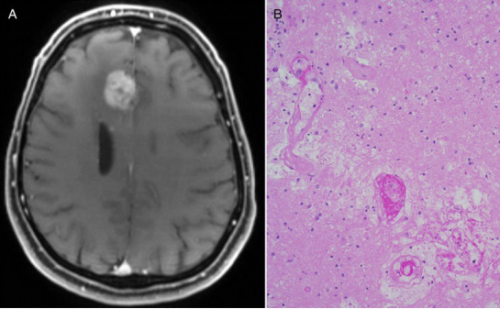

“假性进展”的一个例子:成像表明患有胶质母细胞瘤的患者在疫苗免疫治疗后肿瘤生长,但肿瘤样本分析表明治疗确实杀死了大部分肿瘤。Credit: BMC Medicine December 2015. doi: 10.1186/s12916-015-0536-8. CC BY 4.0.